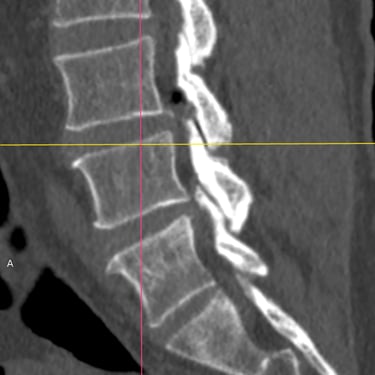

Inestabilidad de la Columna Lumbar: Tratamiento con Fijación Transpedicular y TLIF

La inestabilidad de la columna lumbar ocurre cuando los segmentos vertebrales pierden su alineación y soporte normal, generando dolor lumbar crónico, limitación funcional y, en algunos casos, compresión de las raíces nerviosas. Cuando el tratamiento conservador no resulta efectivo, la fijación transpedicular (FTP) asociada a la fusión intersomática transforaminal (TLIF) representa una alternativa quirúrgica eficaz. Este procedimiento permite estabilizar el segmento afectado, descomprimir las estructuras nerviosas y restaurar la biomecánica de la columna. La combinación de fijación y fusión reduce el dolor, mejora la estabilidad vertebral y favorece una recuperación funcional segura y progresiva.